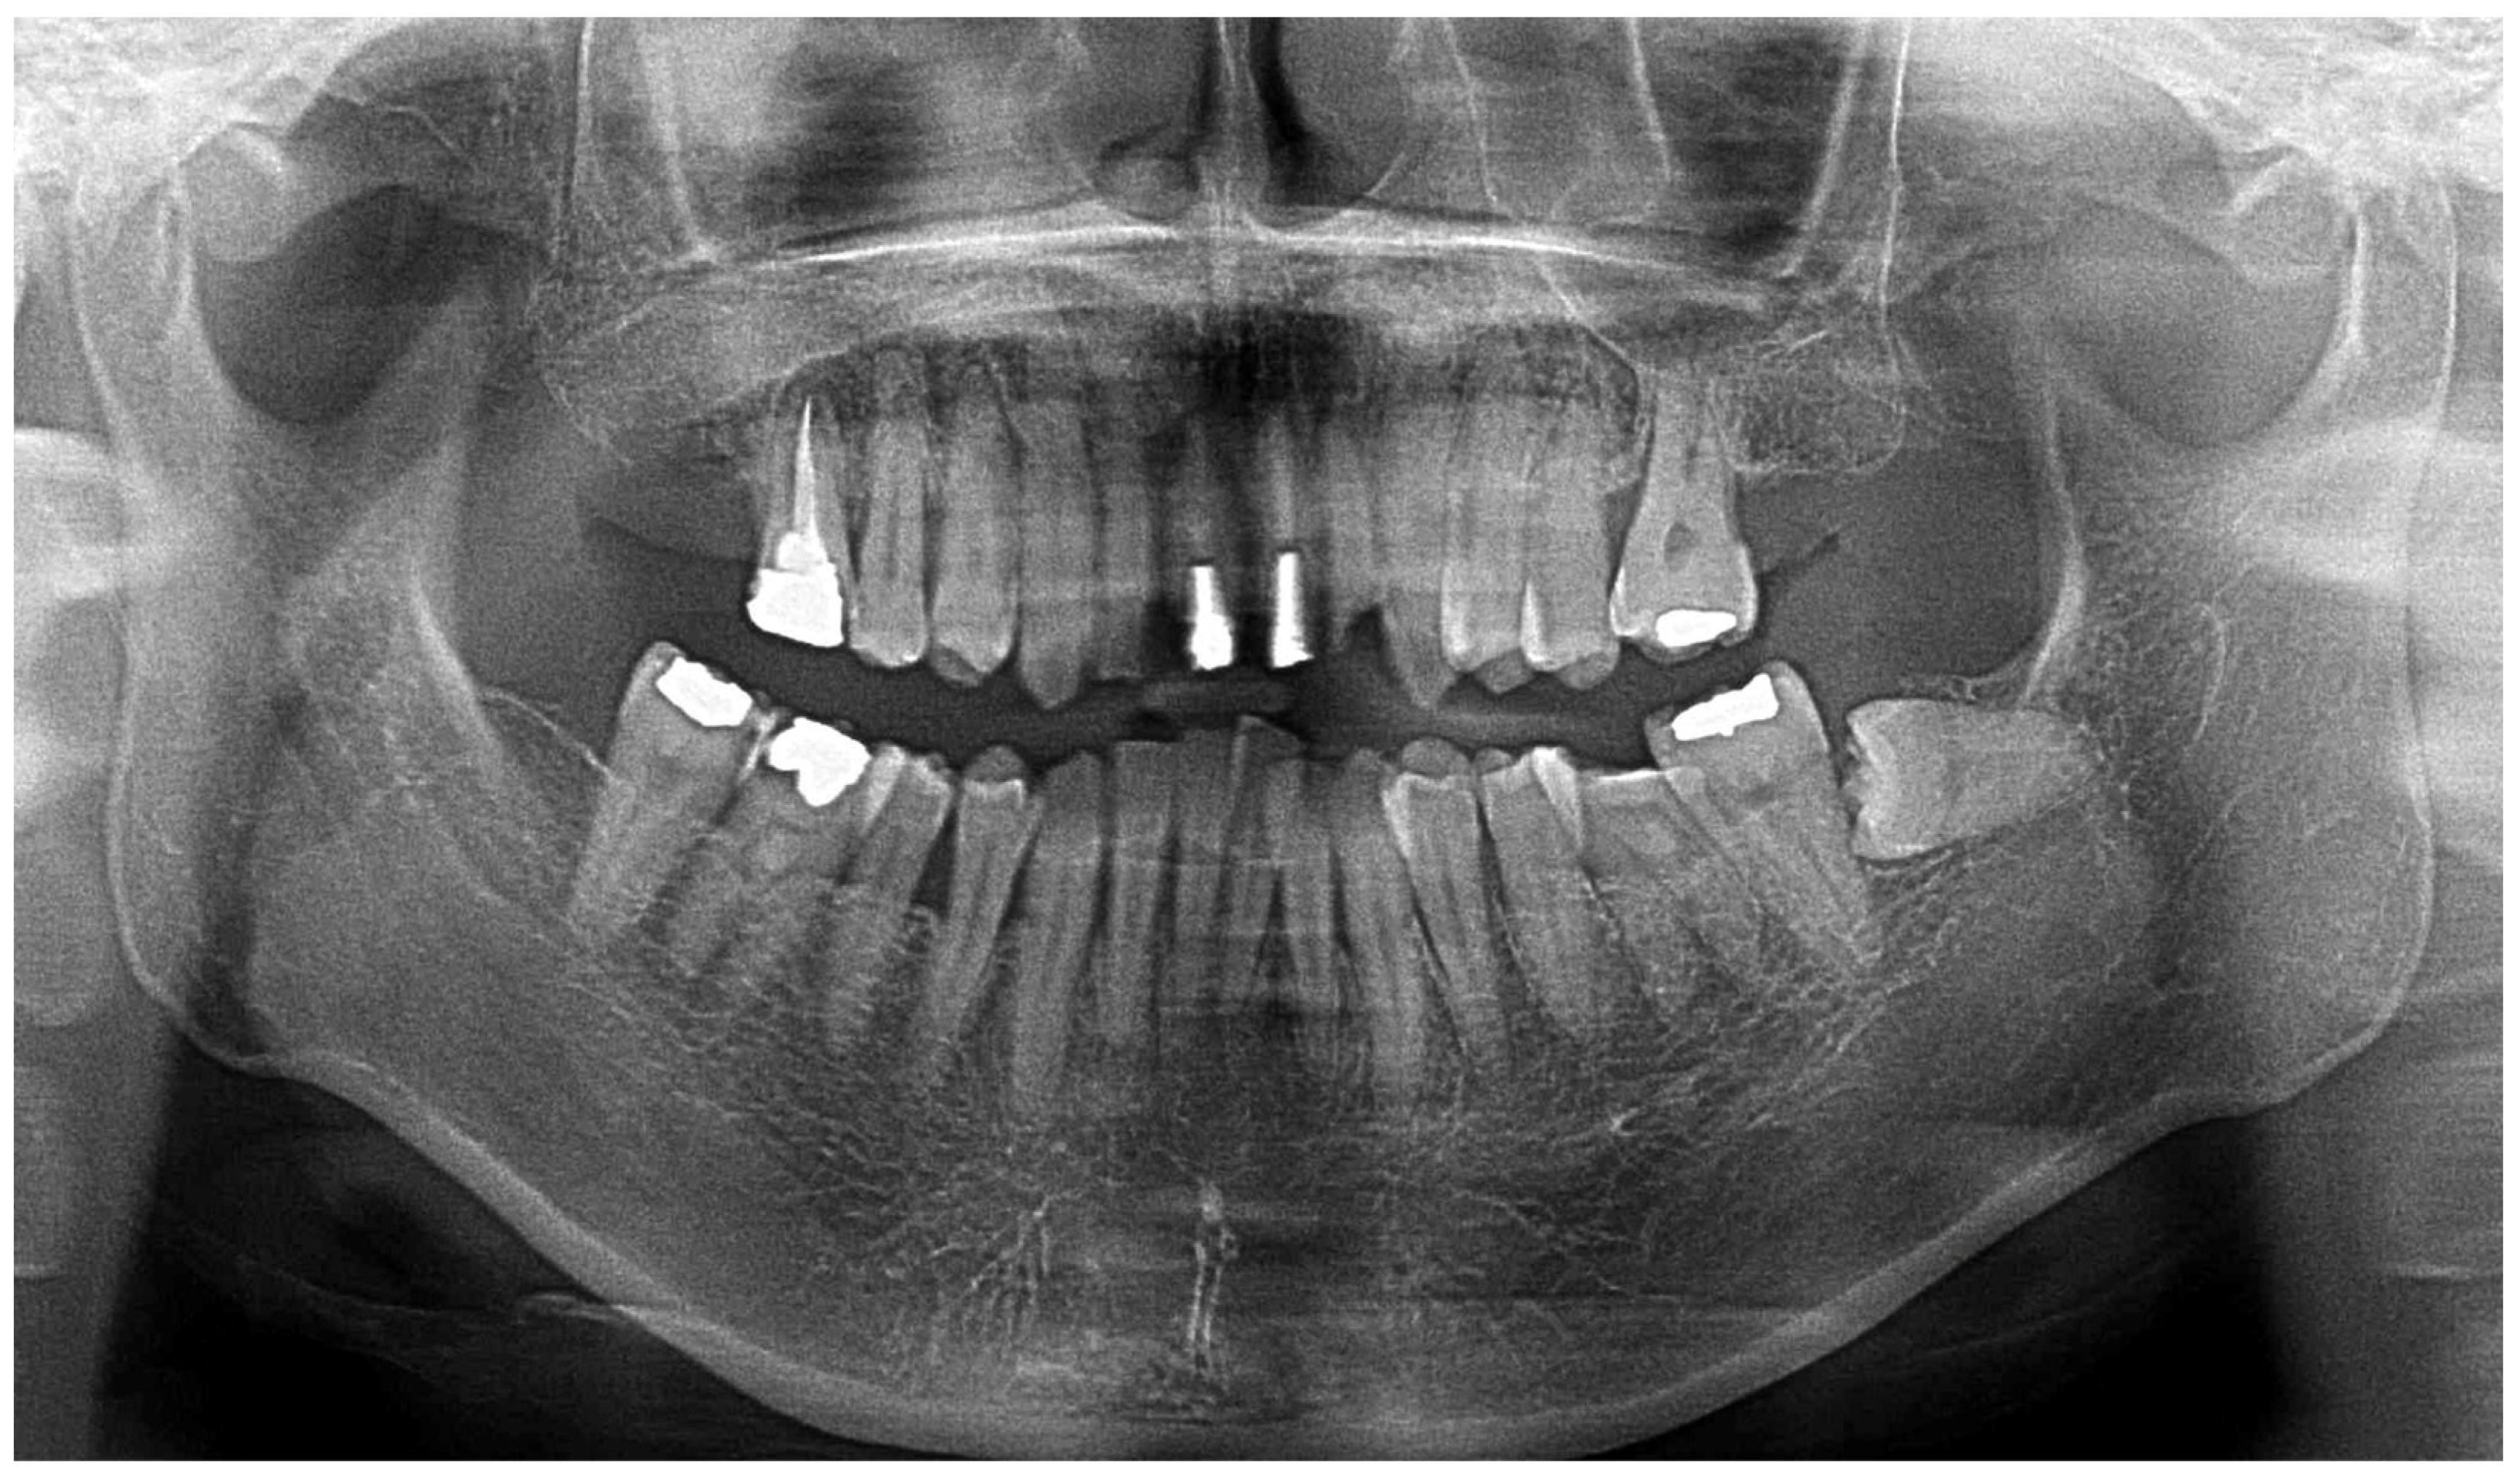

At the time of the initial examination, the porcelain-fused-to-metal restorations of the maxillary bilateral central and maxillary left lateral incisors were detached, and the maxillary left lateral incisor was affected by caries (Figure 1). A sinus tract was found on the buccal side of the maxillary right central incisor. Crowding was also observed in her dentition. The maxillary bilateral second molars had been extracted, and the maxillary right first molar and mandibular bilateral first molars were under treatment, resulting in a significant decrease in occlusal support in the molar regions (Figure 1 and Figure 2). Periodontal examination revealed extensive plaque accumulation throughout the dentition, with a plaque control record of 75% (Figure 3a). Periodontal pockets of 6–7 mm and suppuration were observed in the maxillary bilateral central incisors. Radiographs showed radiolucency around the roots of the maxillary bilateral central incisors and a fracture line around the center of the roots (Figure 3b). Marked alveolar bone resorption was observed around multiple teeth, including the maxillary bilateral lateral incisors. Based on the examination results, the patient was diagnosed with bilateral maxillary central incisor root fracture, malocclusion (classified as Angle class 1 with crowding), and stage 4 periodontitis (grade C).

Figure 2. Panoramic radiograph at the initial examination.

Diagnostics 15 00765 g002